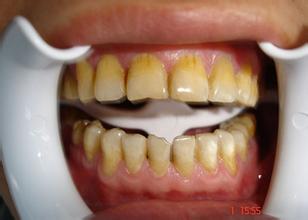

四环素牙主要是指服用了四环素类药物导致的牙齿变色脱矿,它随着病变的严重程度不同而呈现出黄色、灰色甚至是灰褐色等,对美观的影响很大。那么四环素牙能变白吗?

对此,康贝佳口腔医院医师表示,四环素牙是能变白的,常见的使四环素牙能变白的方式主要有以下几种: